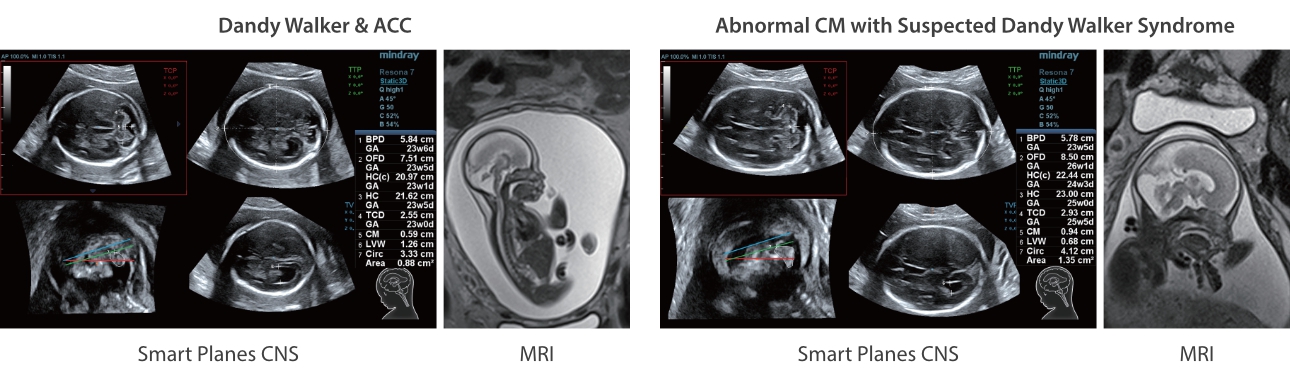

Neben der erstklassigen Bildqualit?t verbessert Resona 7 auch die klinischen Forschungsm?glichkeiten mit dem revolution?ren V Flow f├╝r die vaskul?re h?modynamische Bewertung und der intelligentesten Ebenenerfassung aus 3D-Datens?tzen f├╝r die f?tale ZNS-Diagnose. Mit der Kombination aus intuitiver, gestenbasierter Multi-Touch-Bedienung und allen wichtigen klinischen Funktionen ist das Resona 7 ein echter Wegbereiter f├╝r neue Ultraschall-Innovationen.